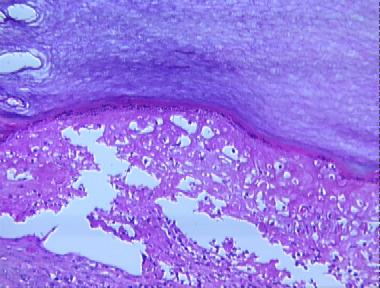

hand-foot-mouth disease

Histologic Features